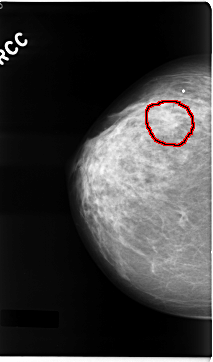

FILE: C_0041_1.RIGHT_CC.OVERLAY

TOTAL_ABNORMALITIES 1

ABNORMALITY 1

LESION_TYPE MASS SHAPE IRREGULAR MARGINS ILL_DEFINED

ASSESSMENT 4

SUBTLETY 3

PATHOLOGY MALIGNANT

TOTAL_OUTLINES 1

BOUNDARY